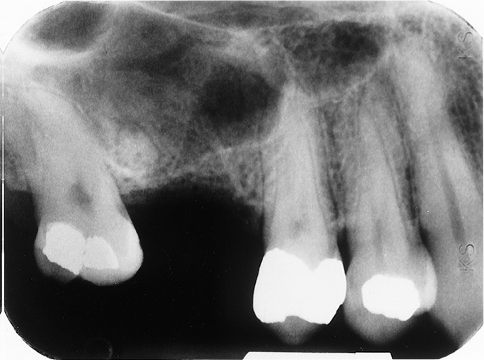

1. (Select ONE OR MORE correct answers)

The radiograph shows evidence of